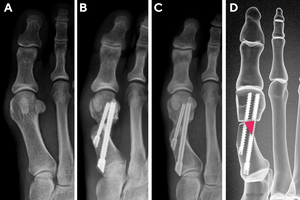

First Metatarsal Regeneration Type I: Callus formation located only medial to the MI anchor bone screw (Figure 2).

_type_i.jpg)